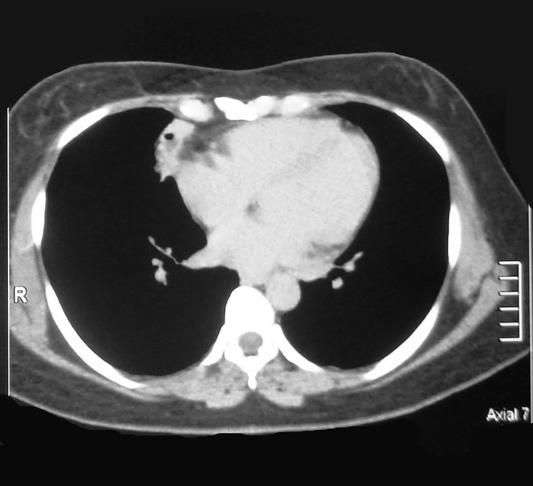

Corte Axial nivel carina bronquial

Corte Mediastinal a la altura de la carina.

Lesión redondeada por delante de aorta ascendente de aspecto homogéneo bien limitada, su cápsula es brillante y bien vascularizada.

Corte Axial nivel hileo pulmonar

Corte Mediastinal a nivel hileo pulmonar.

Lesión redondeada por delante de la aorta y a su derecha la vena pulmonar. contacta con la pared torácica anterior si alterarla.